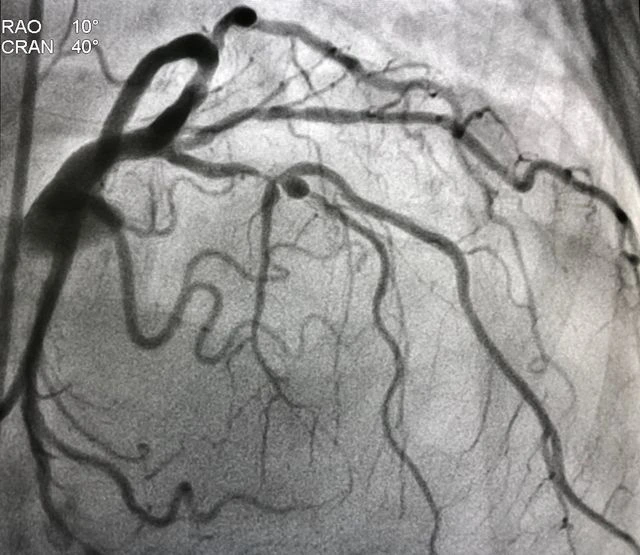

EXPERT DOCTORS AND SURGEONS IN NEW JERSEY FOR: BRAIN, SPINE, NEUROVASCULAR, NEUROLOGY, NEUROPSYCHOLOGY, PAIN, & ORTHOPEDICS

"I thank God and the best Neurosurgeon in the United States, Doctor CIRO RANDAZZO, MD, who through endovascular surgery treated the two aneurysms in my brain, and thanks to his professionalism and extensive experience in the field of brain surgery, I am enjoying excellent physical and mental health and fully developing 100% in my work activity."

- Mercedes Valdivia de Reynaga